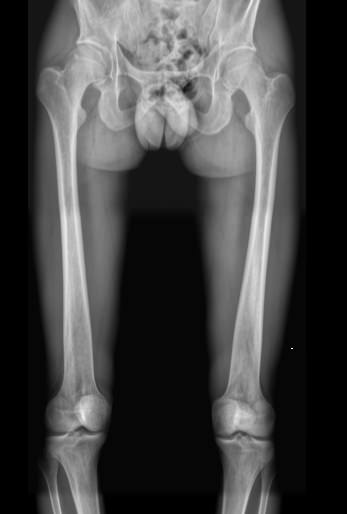

Рентгеновское исследование ― первичный вид диагностики, который назначают при переломах и подозрении на патологию костной ткани. Это неинвазивная, широко доступная и высокоинформативная процедура, во время которой пациент не испытывает никаких ощущений. Полную информацию о состоянии обследуемого участка тела можно получить уже через 10 минут после обследования. При этом современные рентгеновские аппараты излучают минимум ионизирующего излучения, позволяющие безопасно делать множество снимков в год, например, для контроля и коррекции проведенного лечения.

Рентгенограмма необходима хирургу, травматологу или ортопеду для подтверждения или исключения следующей патологии:

• Перелом;

• Остеомиелит и другие воспалительные процессы;

• Патологии мягких тканей;

• Новообразование или метастазирование.

Что показывает рентген обеих бедренных костей в одной проекции

• Травматические повреждения одной или обеих костей ― место перелома, осколки;

• Участки изменений костной ткани, такие как воспаление, гнойное или асептическое, разрежение, размягчение, склерозирование или новообразования;

• Участки поражения мягких тканей, например, кисты, другие новообразования или миозиты, протекающие с оссификацией мышцы.